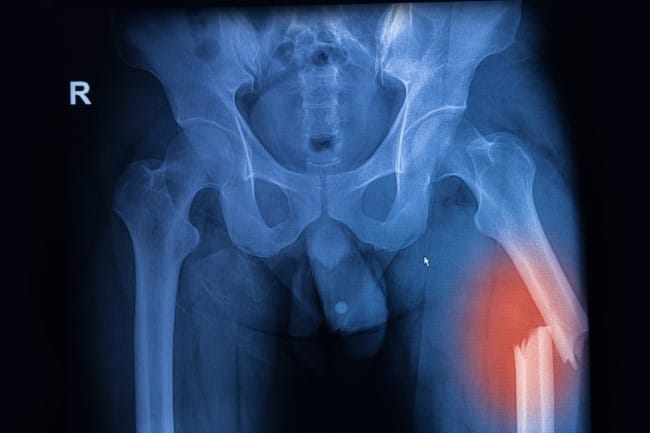

- Foto Rontgen (X-ray), untuk melihat posisi dan tingkat keparahan patah tulang

- CT scan atau MRI, untuk memeriksa lebih rinci terutama jika patah tulang paha sangat kompleks atau melibatkan jaringan ikat, beberapa bagian tulang, maupun sendi sekitar.